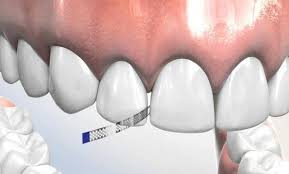

Stripping o cómo ganar espacio para un tratamiento de ortodoncia

El stripping dental es un procedimiento mediante el cual el ortodoncista reduce el ancho de determinadas piezas dentales (entre 0,2 y 0,5 milímetros) para separarlas y ganar así un […]